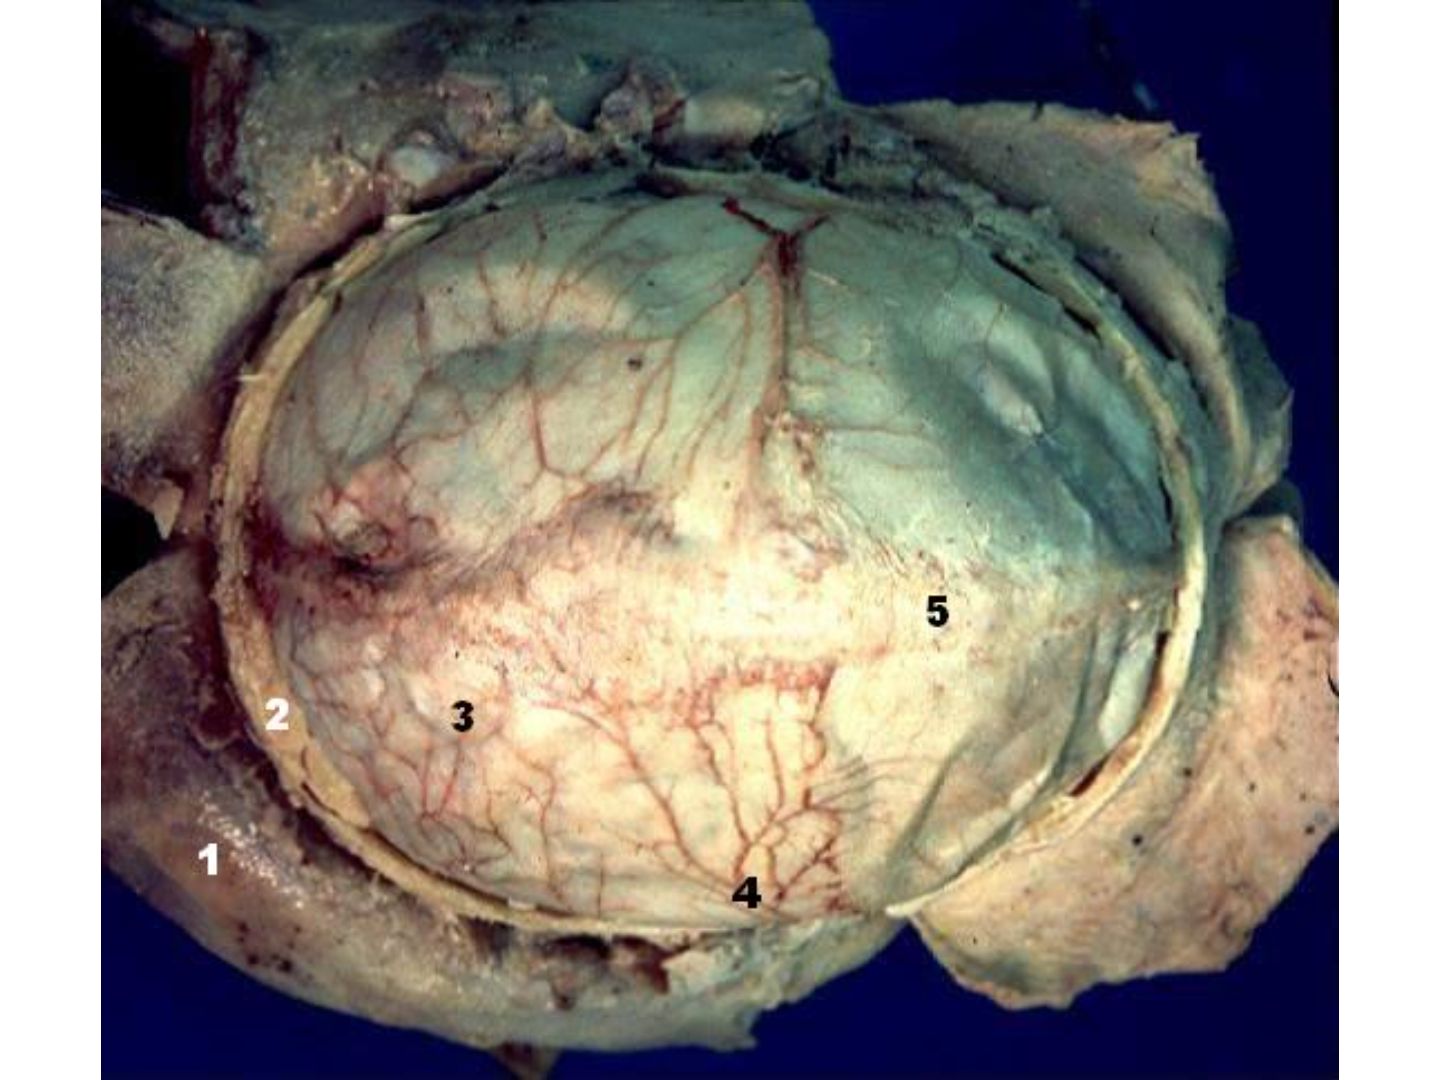

Darstellung der Dura mater nach Entfernung der Schädelkalotte.

Sichtbar sind:

1 – Haut 2 – Knochen 3 – Dura mater 4 – A. meningea media 5 – Sinus sagittalis superior.

Die Dura mater ist die äußere, feste Hirnhaut mit gut erkennbaren meningealen Arterien.

Klinisch bedeutsam ist die A. meningea media, häufige Blutungsquelle beim Epiduralhämatom.

Weitere Äste: A. meningea anterior (vorderer Abschnitt) und A. meningea posterior (hinterer Abschnitt).

Dura mater - Darstellung der Dura mater nach Entfernung der Schädelkalotte.